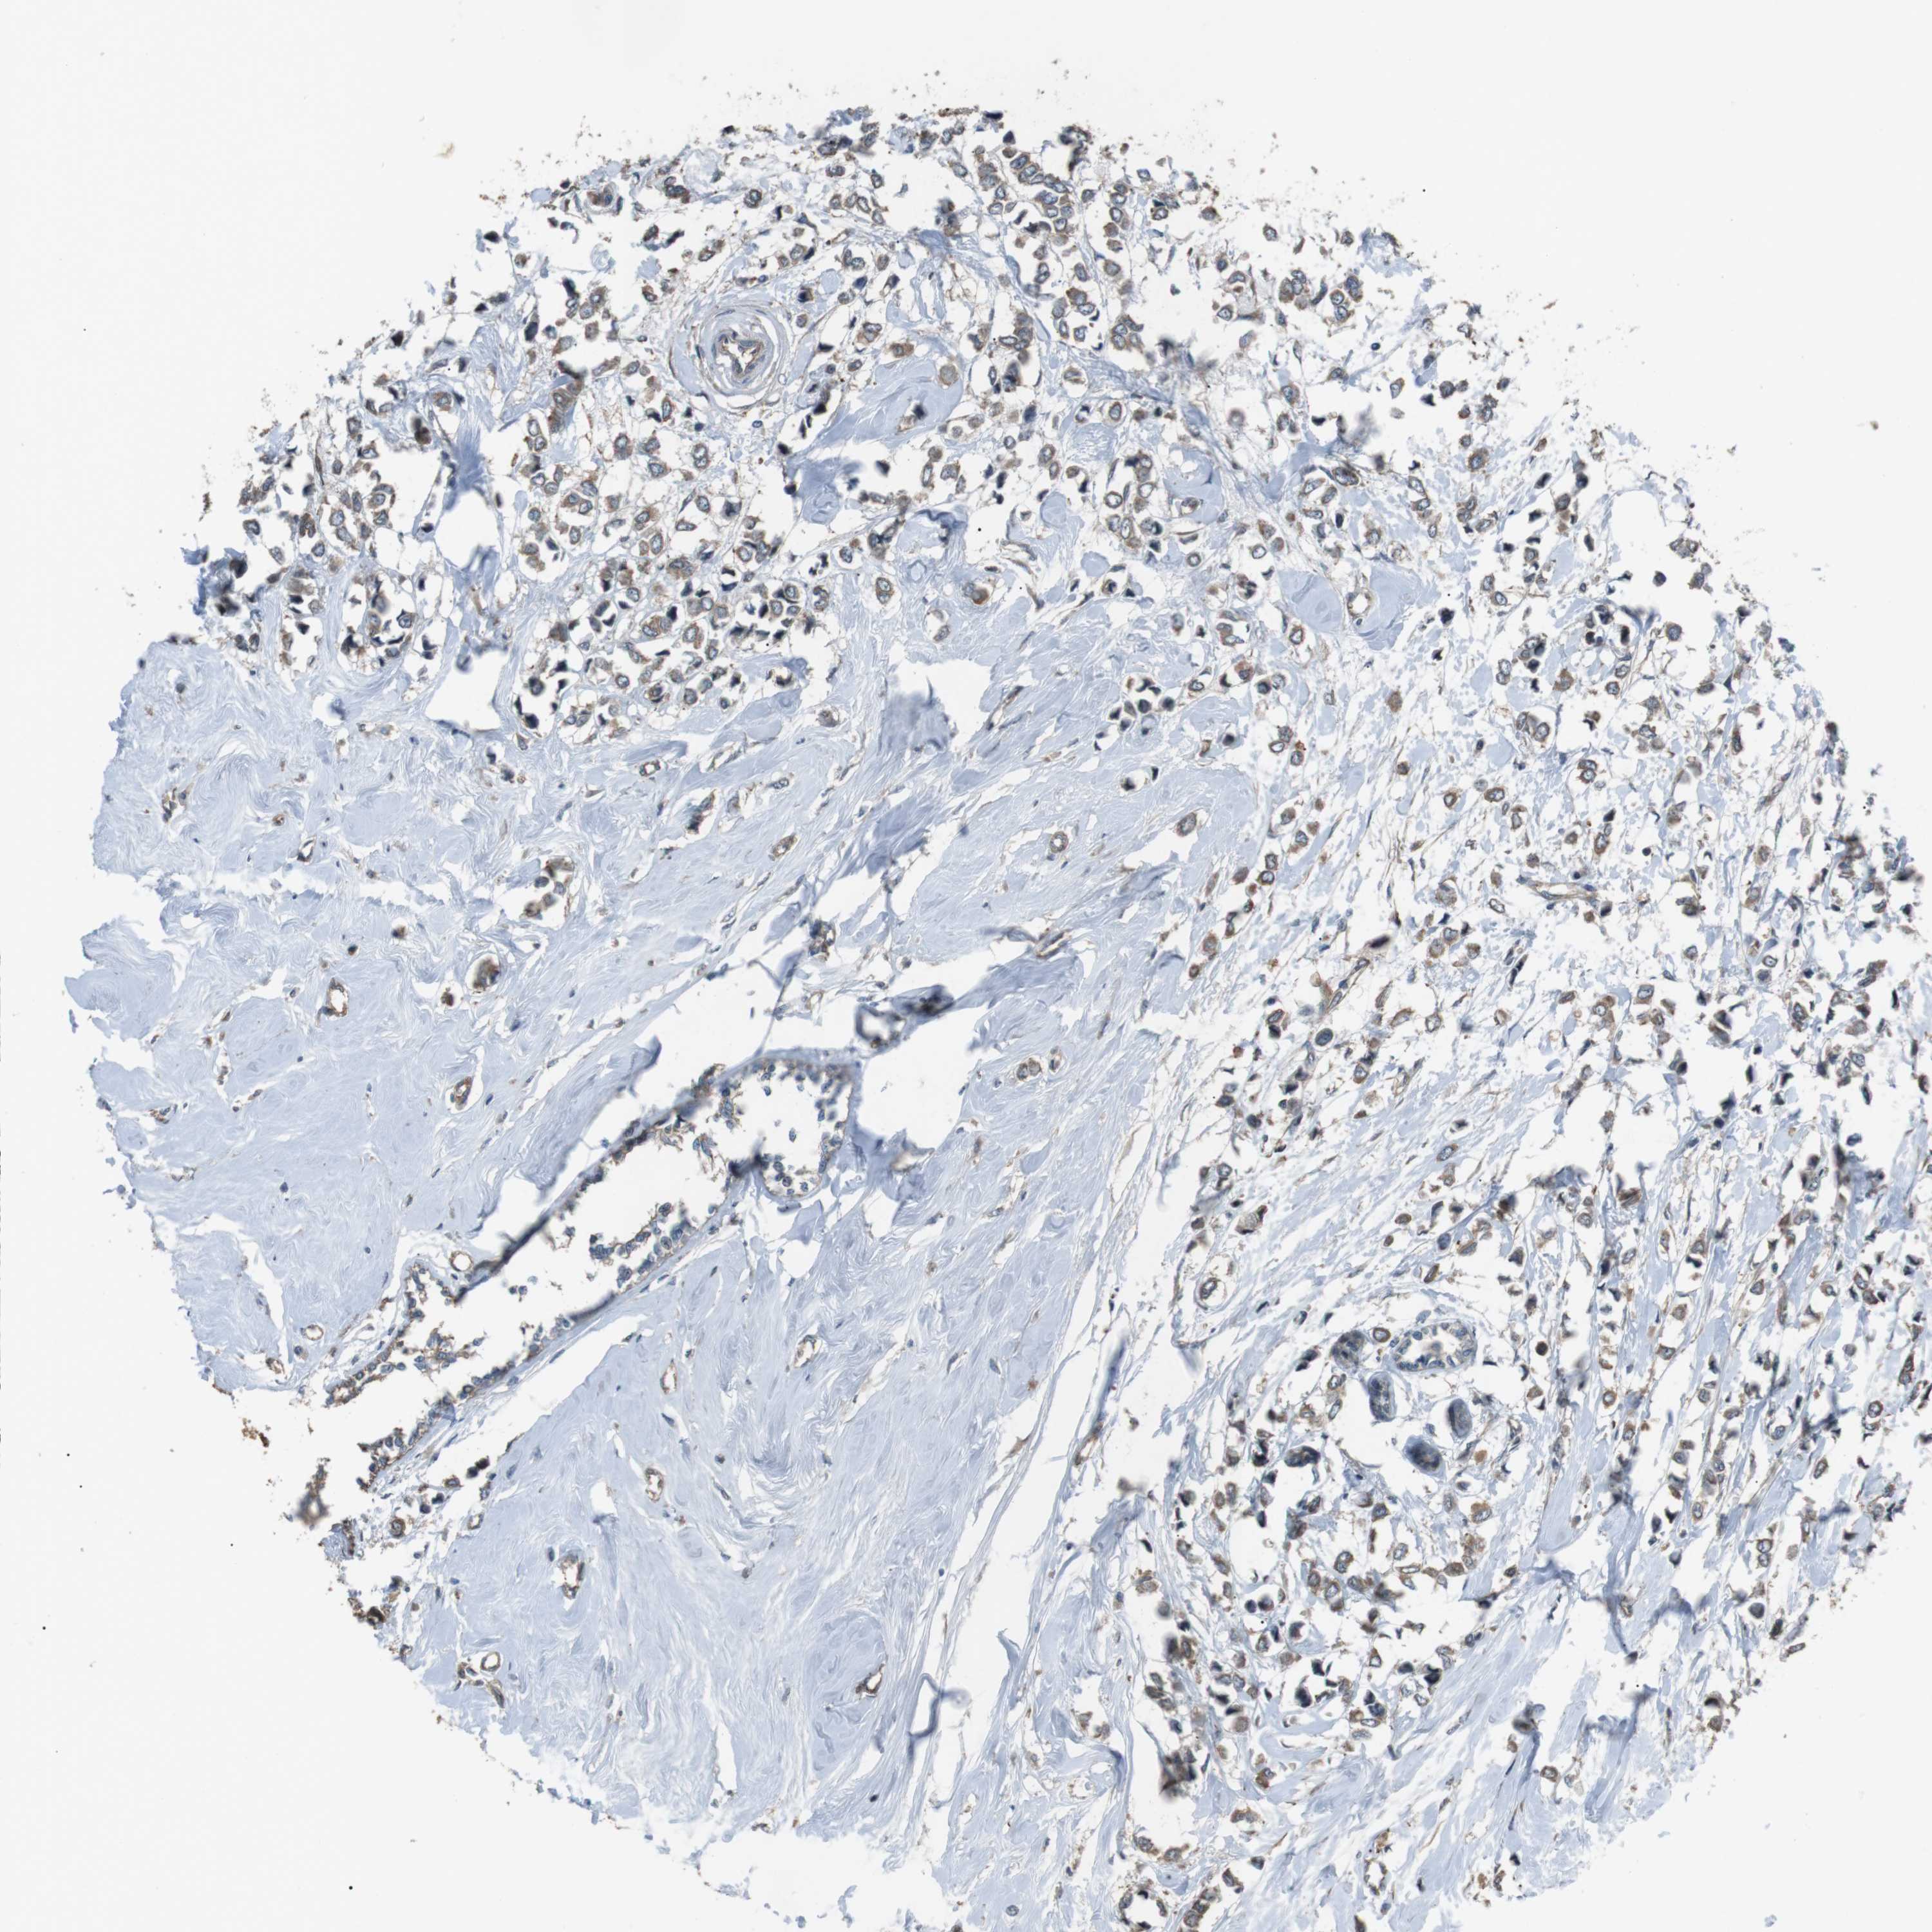

BRCA TCGA BRCA VALIDATION PROTEIN EXPRESSION

ANTIBODIES

AND

VALIDATION